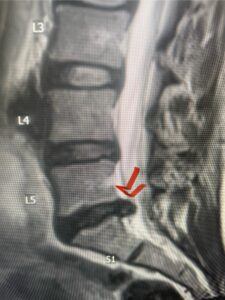

In this next case, this patient is a 47 year-old female who presents with intractable low back pain with severe pain, numbness, and weakness in the right lower extremity that had gotten progressively worse over a year. The patient had failed conservative management including physical therapy and epidurals. She was noted to have ⅘ weakness of plantar flexion. MRI demonstrated a large right L5-S1 disc herniation with severe compression of the descending right S1 nerve root (Fig 3). It was decided to perform a right L5-S1 hemilaminectomy for removal of the disc fragment and decompress the S1 nerve root. When you expose the disc, one must be certain to release any anterior adhesions to the nerve root in order to prevent a dural tear during retraction of the nerve root. It is also important to make sure during exposure and you finally encounter the dura after removing the ligamentum and fat, to make sure you are looking at the nerve root and not the main trunk of the thecal sac because if you don’t you can avulse or damage the nerve root if you retract the wrong structure.

Fig. 3a: Sagittal and axial T2-weighted lumbar MRI images demonstrating large right L5-S1 disc herniation (red arrows)

Fig. 3b